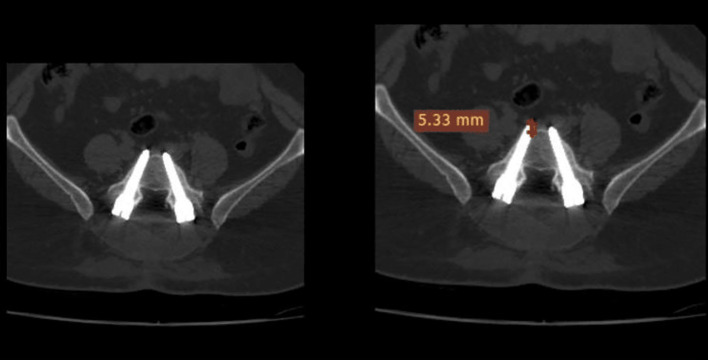

Objectives: Our study aimed to evaluate the reliability and validity of the use of a new scoring system (the Meshtawy Pedicular Screw Malposition - MPSM) for evaluating pedicle screw misplacement by a detailed clinical-radiographic comprehensive scoring system (MPSM) with sharp guidance for treating injurious violations by assessing the correlation between the neurological data of patients and computed tomography (CT) findings.

Patients and methods: This prospective case series included 100 patients (508 pedicular screws) who underwent transpedicular fixation at Orthopedic department Al-Azhar University Hospital, Assiut branch, Egypt 255 (50.2%) screws were inserted on the right side, while 253 (49.8%) were inserted on the left side. Intra-observer reliability was examined by calculating Cronbach's alpha intraclass correlation coefficient, which compares three measurements obtained by each observer at different time points. Inter-observer reliability was also examined by calculating Cronbach's alpha intraclass correlation coefficient and comparing the average measurements obtained by each observer.